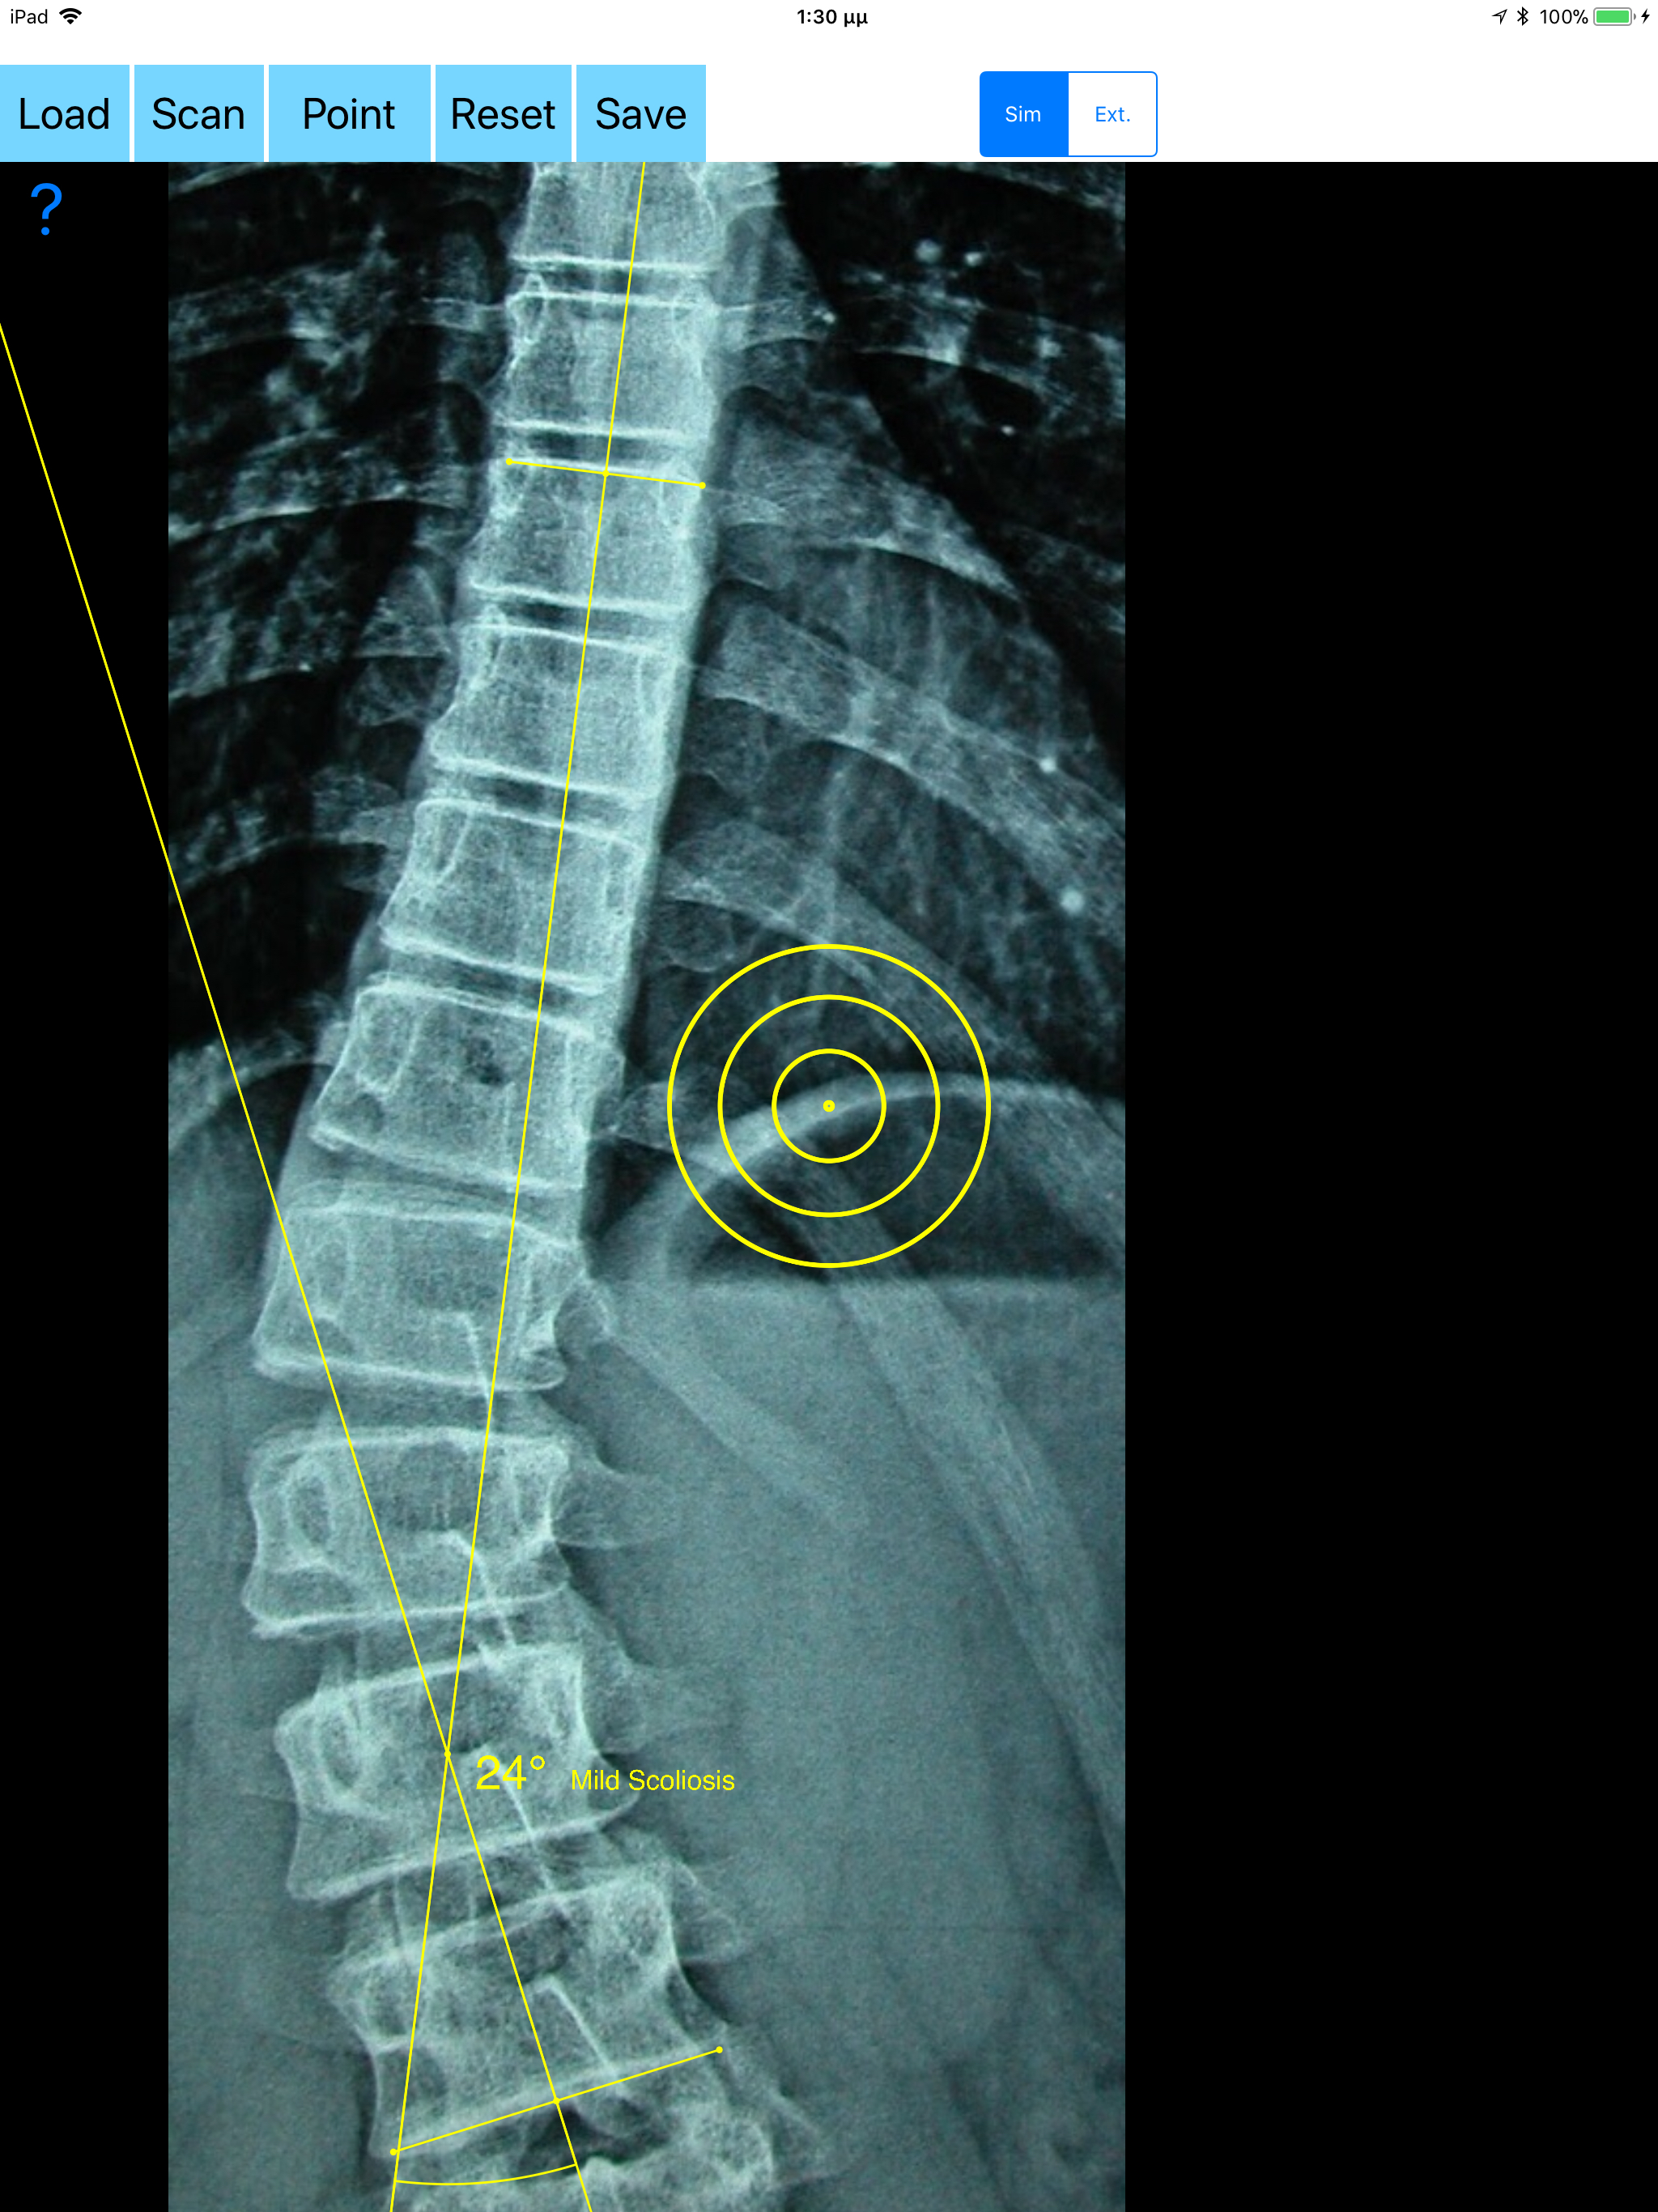

Cobb method is considered the standard for measuring curve size in scoliosis. Cobb angles are always measured from the superior end plate of the most cephalad end vertebra to the inferior end plate of the most caudal end vertebra in the curve. Meticulous line drawings and precise measurements is paramount importance in order to quantify the magnitude of spinal deformities and monitor the success or failure of treatment for scoliosis. The CobbAngleApp is medical software aimed for orthopaedic surgeons, providing tools that allow doctors to: -Securely import medical images directly from the camera or stored photos. -Offers a very convenient way to determine the most accurate possibly way at once. By marking four points at the same X-ray, at each spine the App calculates the Cobb angle. In cases where values are out of normal ranges, the scoliosis is categorized according to measured angle as mild, moderate, severe. To simplify the process and to minimize inter-observer errors usually by not selecting the actual end vertebra, the app offers also in ext mode the ability to draw the vertical reference line through the patient’s sacrum and to identify more easily the end vertebrae s (ext method). -Save the planned images, the measured values and results compared by normal reference databases, for later review or consultation. -The app also is independent from errors produced by image inclination. Especially developed module allows the user to measure accurately without to worry about the tilting of the picture or the X-ray. All information received from the software output must be clinically reviewed regarding its plausibility before patient treatment! CobbAngleApp indicated for assisting healthcare professionals. Clinical judgment and experience are required to properly use the software. The software is not for primary image interpretation. In a busy everyday practice, the examiner have to draw lines in X-rays or in clinical settings, this it is time consuming and cumbersome. Accessory instruments like protractors, hinged goniometers, well sharp pencils, rulers or even transparent papers must be available. The app offers a very convenient and also accurate way to perform most common radiographic measurements for spine, in a blink of an eye in front of your screen. The build in feature of the app, allows results to be categorized may help decide what could be considered normal or pathologic. The app is not a simple goniometer, is an enhanced product which helps to monitor objectively the course of the treatment and evaluate optimally the spine. This App is particular useful especially in clinical settings where you need a quick results without losing time. Please see tutorial videos at the developer’s web site www.orthopractis.com Reference databases 1. Cobb JR. Outline for the study of scoliosis. The American Academy of Orthopedic Surgeons Instructional Course Lectures. Vol. 5. Ann Arbor, MI: Edwards; 1948.